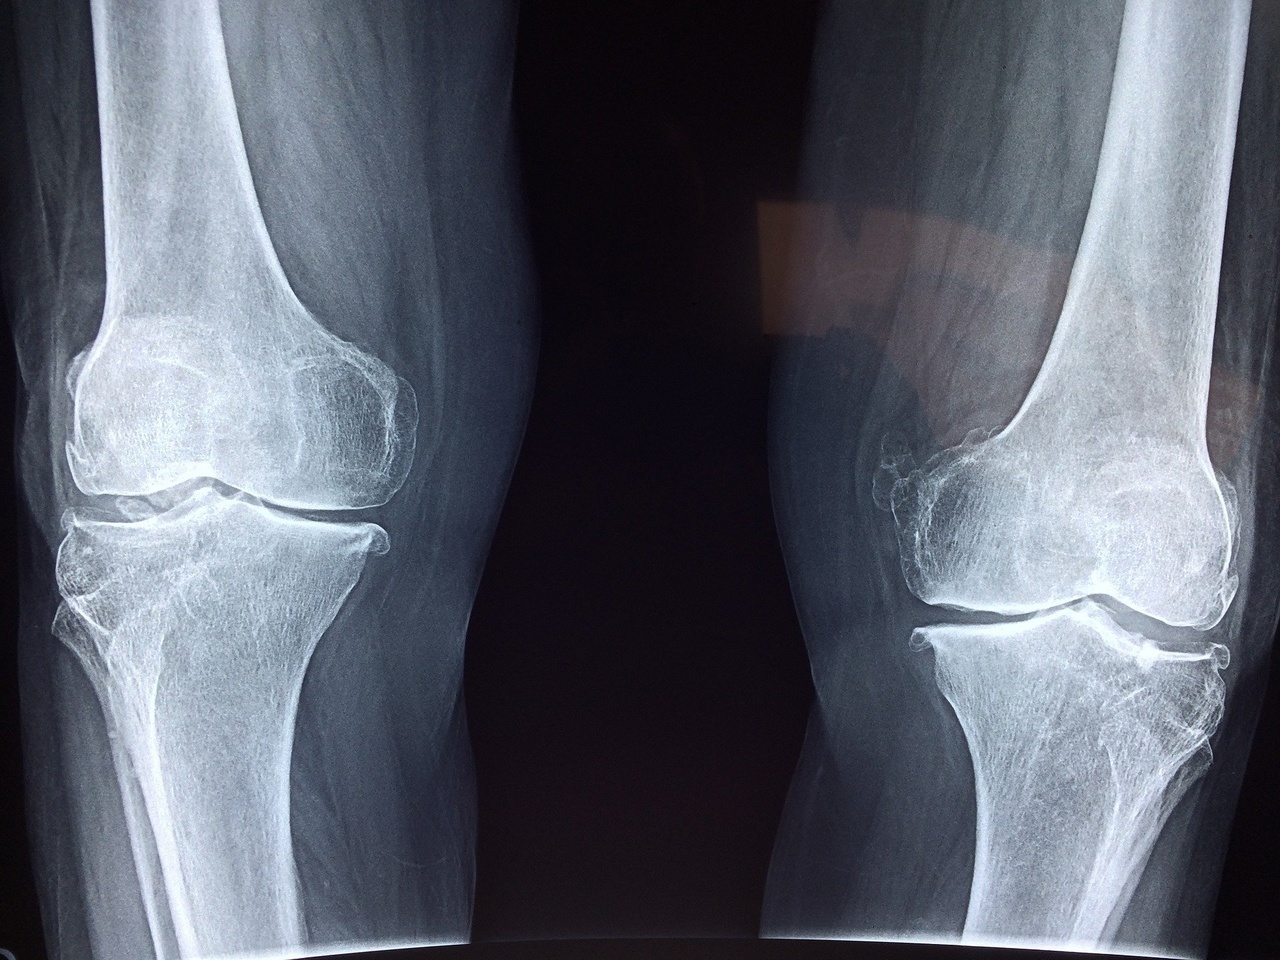

レントゲンを撮ると、関節の隙間がせまくなり、

軟骨が減って骨のトゲ(骨棘)が出ている。

見るからに「痛そう...」と思うはずです。

軟骨のすり減り・変形が痛みの原因だと言われ信じてしまう

レントゲンだけで、不安にならないでください。